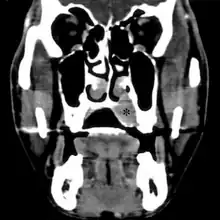

Extraskeletal Ewing sarcoma hard palate

Top: Ewing sarcoma of the thigh bone on a child's CT scan

Bottom: Extraskeletal Ewing sarcoma of the hard palate